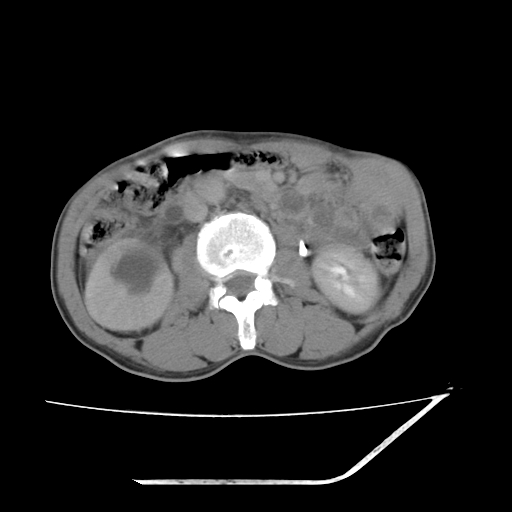

平扫

增强

考虑右肾盂癌,肾动脉受侵,右肾功能减退,右肾盂输尿管积水,管壁增厚,考虑种植转移,应该把下面扫完的

支持右侧肾盂癌伴肾静脉瘤栓形成可能性大,右肾结石.肝右叶后段低密度影,不除外转移.

考虑右侧肾盂癌。右侧输尿管扩张未扫描完。

右肾盂旁ca并肾静脉瘤栓形成/肾功能降低。

右肾结石。

右肾盂癌,肾动脉受侵,右肾盂输尿管积水,管壁增厚,考虑种植转移

右肾盂移行细胞癌并右输尿管中段转移.肾积水.

1.右侧肾盂癌伴肾盂积水。

2.肾脏功能减退,原因有:(1)肾动脉受侵。(2)肾静脉受侵(3)肾积水,等。本例,肾动脉显影较好,但受压明显;肾静脉无明显显示,受压或静脉癌栓,下腔静脉腔内未见明显充盈缺损。

3.右侧上段输尿管扩张,原因:(1)积水所致;(2)种植。